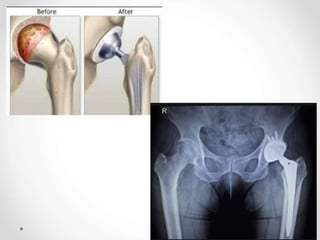

Pencitraan radiologis sinar-x osteoarthritis pada pinggul

Kedua gambar di atas menunjukkan penyempitan ruang superolateral

sendi, sklerosis, kista subkondral, dan pembentukan osteofit (panah)

Sumber : Jacobson, JA, et al. 2008. Radiographic Evaluation of Arthritis : Degenerative Joint Disease and Variation. Radiology. 248(3) : 737-747.

Pencitraan radiologis sinar-x osteoarthritis pada panggul

Rheumatoid arthritis dengan osteoartritis sekunder. Gambaran radiologis

panggul anteroposterior menunjukkan penyempitan ruang sendi setiap

sendi panggul. Perhatikan erosi (anak panah) dan osteofit (panah)

Gambaran sendi panggul normal Adanya pembentukan osteofit pada

sendi panggul